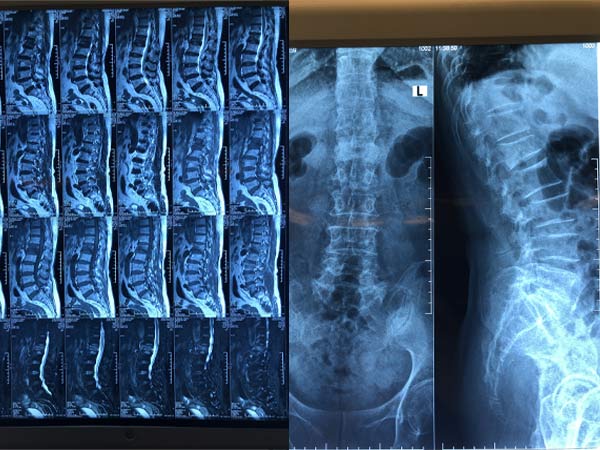

Chẩn đoán hình ảnh là quyết định để đánh giá VF. Xquang cột sống ngực thắt lưng thẳng nghiêng thường quy thường được sử dụng nhất để đánh giá ban đầu VF. Tuy nhiên chỉ xquang thường không đánh giá được hết mức độ và tổn thương. MRI thường được chỉ định, nó có thể xác định được chính xác xẹp đốt sống cấp và bán cấp tính, đánh giá hình thái của VF, và phát hiện được một số bệnh kèm theo có thể là chống chỉ định của VP. Thêm vào đó, những đốt sống VF kín đáo khó phát hiện trên Xquang có thể được phát hiện dưới MRI giúp tránh bỏ sót tổn thương. Hình ảnh đốt tổn thương trên MRI do sự phù tủy xương cấp tính, bán cấp tính hoăc VF không được chữa lành, có hình ảnh giảm tín hiệu trên thì T1, tăng tín hiệu trên thì T2 và STIR.

Với bệnh nhân không thể chụp MRI, xạ hình xương có thể được chỉ định để phát hiện đốt sống xẹp cấp tính. CT cũng có thể được chỉ định để xác định VF, hơn thế nữa CT còn dùng để đánh giá tường sau của đốt sống và đánh giá các mảnh xương vỡ.